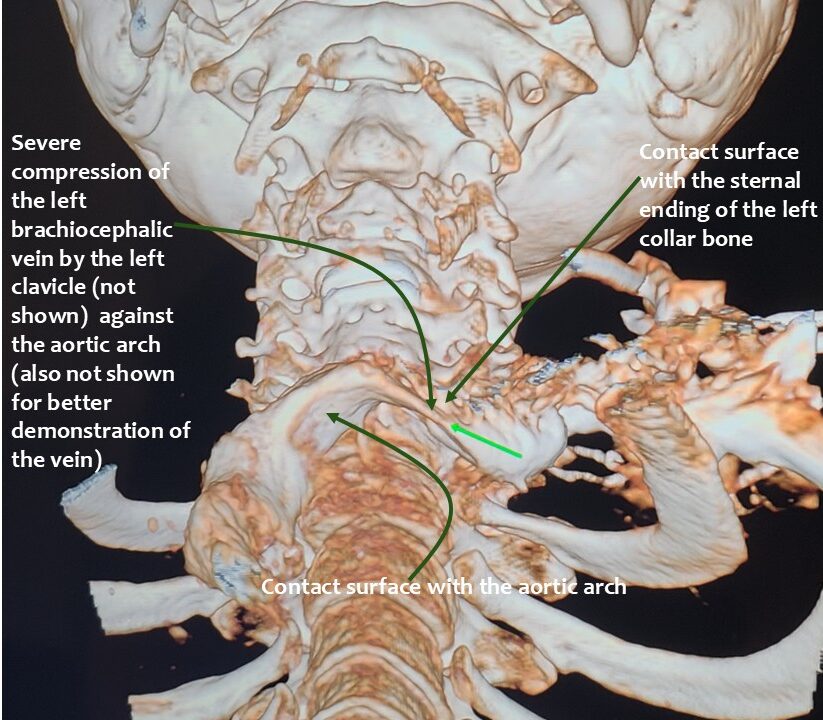

The cause was compression of the left renal vein, the left common iliac vein, both jugular veins and the left cephalic vein.

In addition, the patient had compression of the left brachiocephalic vein.